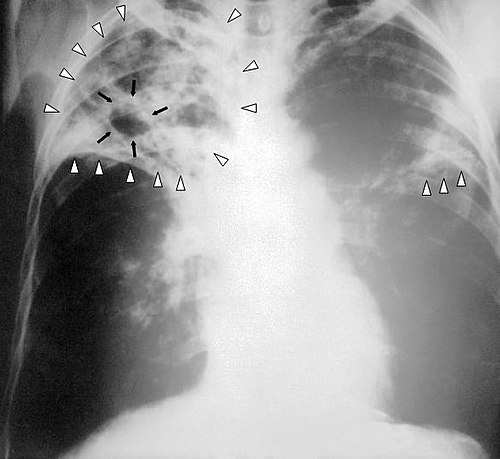

Diagnostic pathways use clinical assessment supported by chest radiography and microbiological methods developed and validated at centers such as Royal Infirmary of Edinburgh, Karolinska Institutet, University College London Hospitals, Johns Hopkins Hospital. Laboratory confirmation employs sputum smear microscopy, mycobacterial culture in laboratories accredited by Clinical and Laboratory Standards Institute, molecular assays such as Xpert MTB/RIF pioneered with partners including Foundation for Innovative New Diagnostics, Cepheid, FIND, and whole-genome sequencing capabilities at Wellcome Sanger Institute, Broad Institute, European Nucleotide Archive-associated facilities.